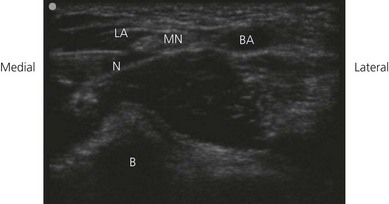

The examination begins with the patient supine, the arm abducted, the forearm supinated, and the wrist halfway between pronation and supination (Fig. 21.5). A systematic survey should be performed from superficial to deep and medial to lateral. A high frequency ultrasound transducer is used. With a transverse orientation, the median nerve is found medial to the brachial artery at the elbow as a hyperechoic structure (Fig. 21.6). This is on the medial side of the antecubital fossa. The radial nerve, after winding around the humerus, descends in the intermuscular septum between the brachialis and brachoradialis initially, and then the extensor carpi radialis. The radial nerve is easily seen with ultrasound, as the deep and superficial branches between the brachioradialis and brachialis muscles at the elbow. This nerve appears as a hyperechoic oval structure on the radial side of the antecubital fossa. The two key structures to identify include the hypoechoic brachioradialis and brachialis muscles. The radial nerve lies in the fascial thickening between these (Fig. 21.7). The ulnar nerve is seen posterior to the medial epicondyle at the elbow level in the condylar groove (Fig. 21.8).

Figure 21.6 Sonosatomy relevant to median nerve block at the elbow. MN: median nerve; BA: brachial artery; B: bone.